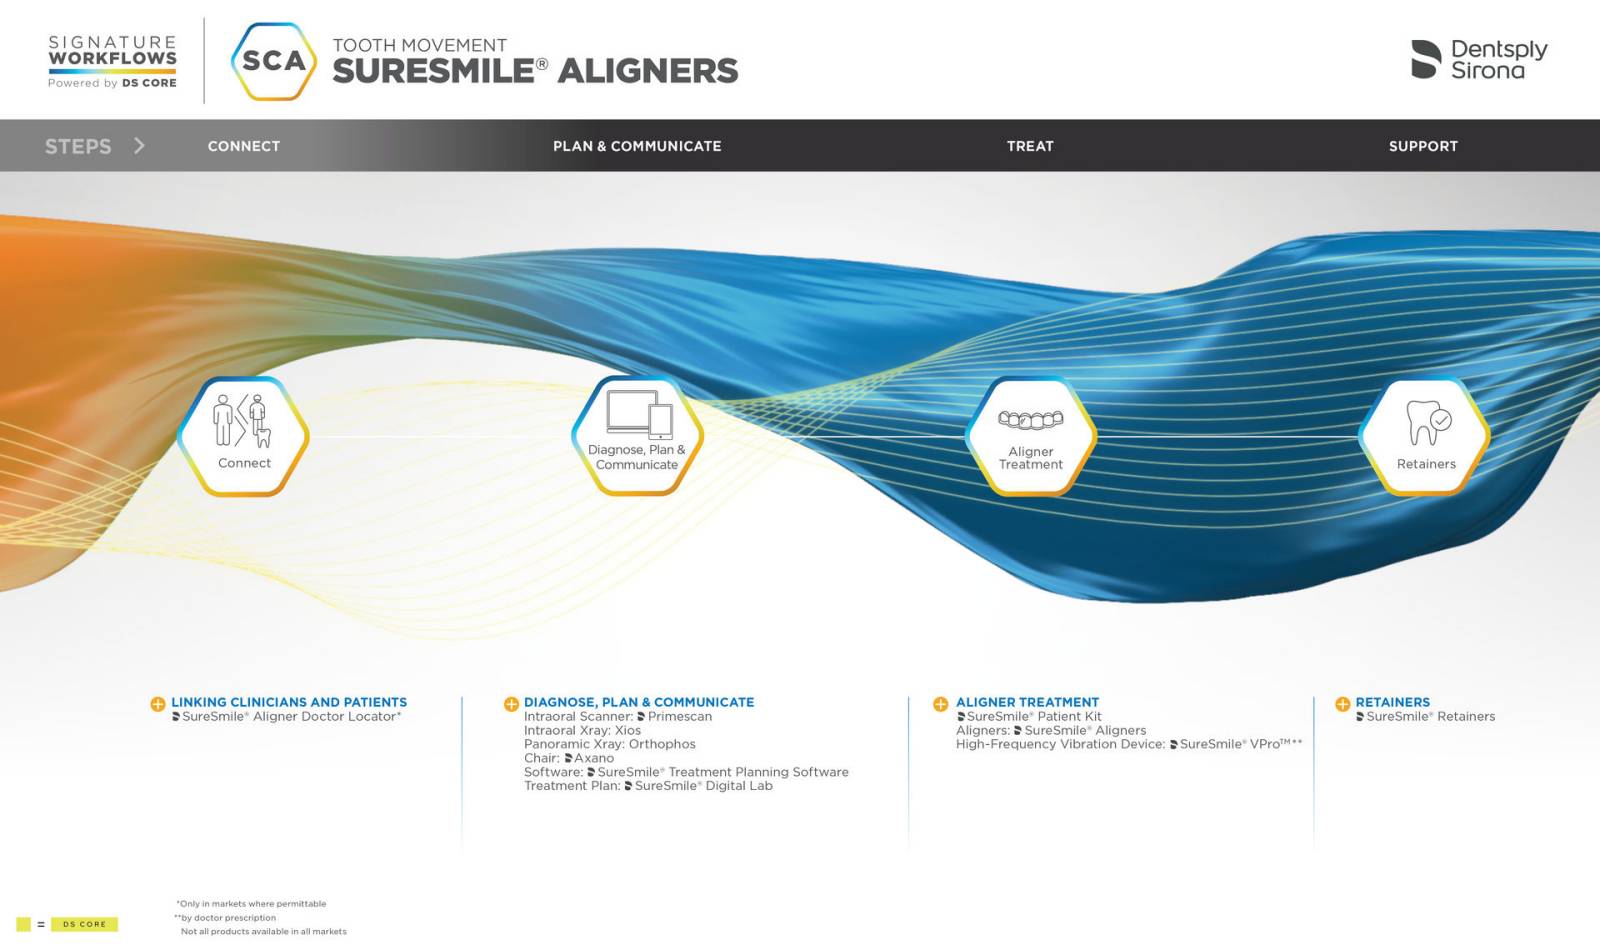

SureSmile® Clear Aligners by Dentsply Sirona are part of a complete clear aligner treatment system incorporating state-of-the-art methodology, advanced digital impression technology, and proprietary software to create a unique patient care experience for both general dentists and orthodontists.

SureSmile® Clear Aligners are made from a high-performance material that is both comfortable and virtually transparent. Patients appreciate that they can easily remove their aligners for eating, brushing, and flossing, making them a convenient and hygienic option for alternative orthodontic treatment. Thanks to predictable workflow systems and preplanned digital mapping, SureSmile® Clear Aligners providers can offer their patients predictable results, making it easier for both dentist and patient to track progress and achieve the desired outcome.

During the initial consultation, dental providers will assess and diagnose their patients’ occlusion and take digital impressions of their teeth using an intra-oral scanner. The scan is then uploaded into the planning software to create a customized treatment plan. SureSmile® software is also open source, so that any intra-oral scanner will work with the system.

Both the Dentsply Sirona Orthophos® and Axeos® imaging systems are compatible with SureSmile® planning software, allowing providers to communicate records with the SureSmile® Digital lab. Dentsply Sirona’s cloud-based system DS Core® is also a benefit for dentists, as patient files can be easily accessed from anywhere.1 This resource makes it easier for dentists to review treatment plans and make updates as needed through the cloud, even if they are not in the office. It also allows for seamless collaboration between dentists, as files can be easily shared and discussed among colleagues in addition to the SureSmile® Digital Lab.

Step 2: Treatment Planning and Case Acceptance

Patient education and engagement are key components of successful orthodontic treatment and case acceptance, even if it’s an elective procedure. During the initial consultation, be sure to discuss your patients’ individual goals and concerns and tailor the treatment plan to their unique needs. Once a treatment plan is created, the Dentsply Sirona SureSmile® software provides a virtual representation for your patient to preview their predicted treatment outcome. Being able to visualize and fully understand their treatment plan may aid in a higher rate of case acceptance, so that patients will proceed with a provider’s care recommendations. The goal is to provide patients with a positive and empowering orthodontic experience that leads to a healthier, more beautiful smile. With resources like SureSmile® software, Primescan®, Orthophos®, or Axeos® imaging, patients are empowered to make educated decisions and visualize what orthodontic treatment can do for them. This may aid in a higher case acceptance rate, especially given the integration with virtual treatment mapping software at the time of their care planning meeting.

SureSmile® treatment planning software and Digital Lab allow providers to create customized treatment plans for each patient, considering their unique functional needs, and smile goals. Providers can also show the patient the digital impressions from Primescan® so they can have a clear view of the ways their teeth are out of alignment; these resources can help to provide patients with a more accurate estimate of the length of their treatment before committing to orthodontic therapy.